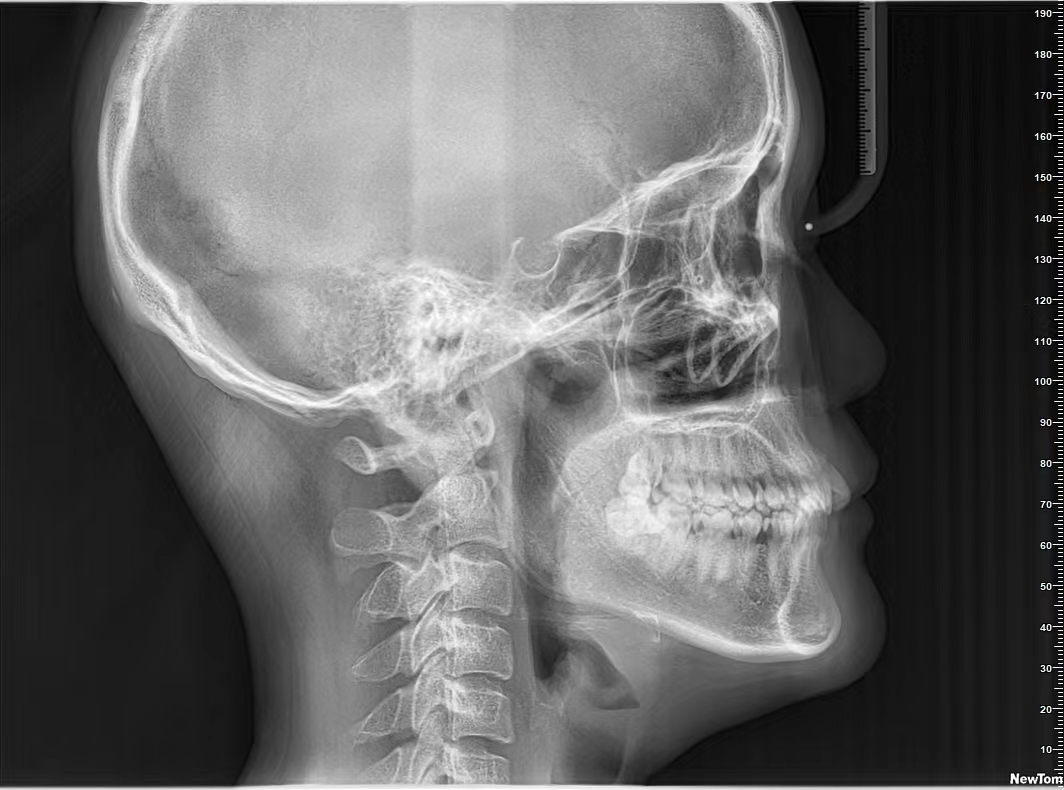

头颅侧位片

头颅侧位片主要用来观察颅骨和上下颌骨的相对位置关系。在口腔正畸方面应用广泛,通过测量特定点组成的角度及长度,为牙齿矫正提供重要的参考指标。头颅侧位片也可观察到颈椎情况,了解小孩处于何种生长发育期。

在正畸治疗中,医生可对矫正前后头颅侧位片进行描记,将前后数据对比,来观察矫正效果,也可找出患者的问题,为后续矫正提供参考。